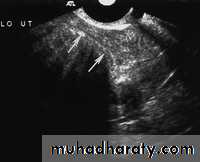

Endometrial hyperplasia. US image shows an endometrium with diffuse thickening (maximum thickness, 1.74 cm) due to hyperplasia (cursors). This finding was confirmed at biopsy.• Pathology of Endometrium